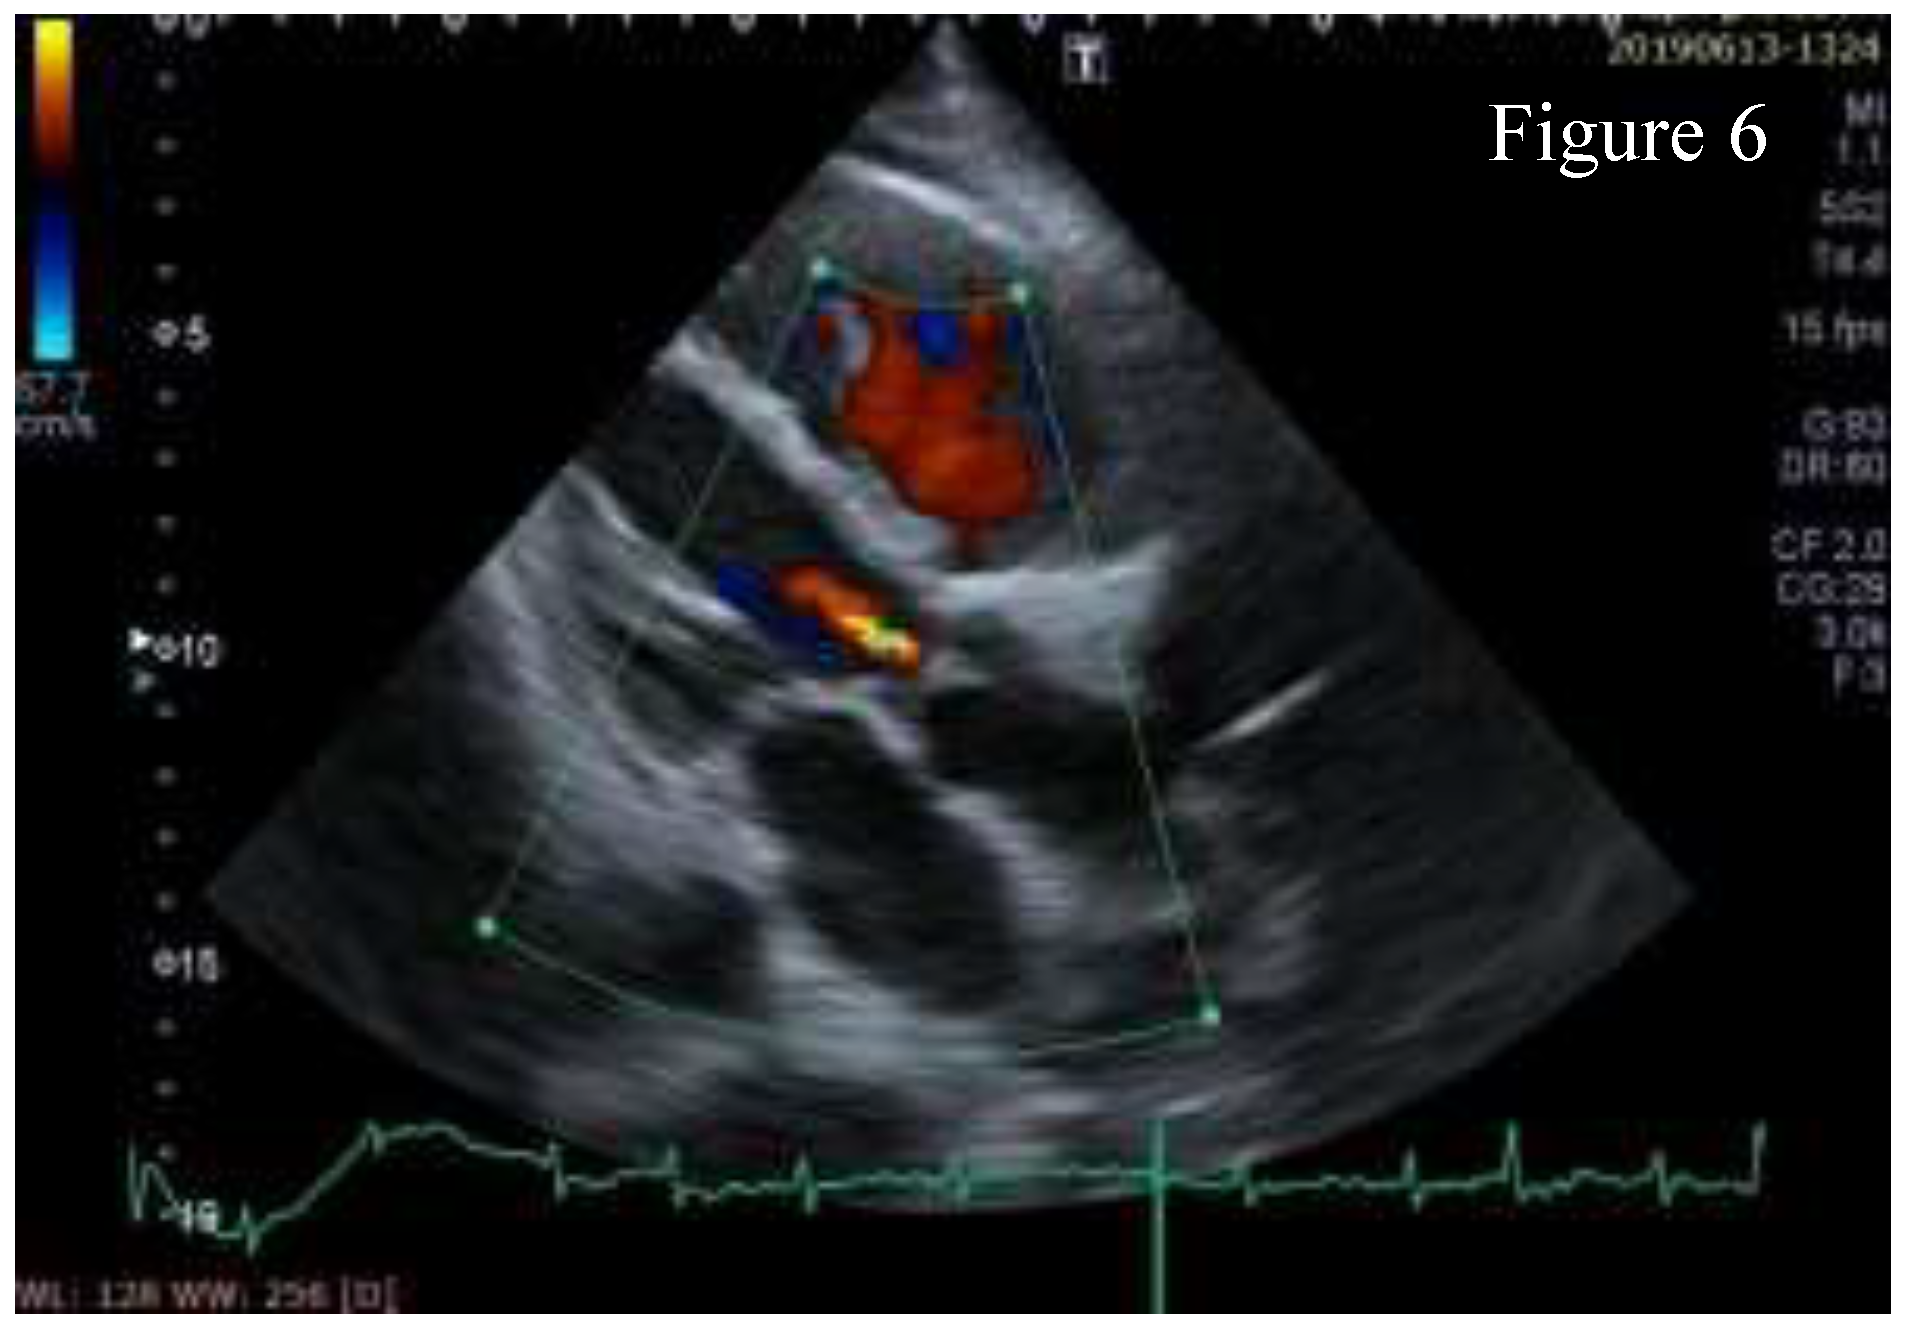

Small calcification spots were found on aortic cusps causing mild aortic regurgitation, aspect shown in Figure 6.

Figure 6.

Mild aortic regurgitation.